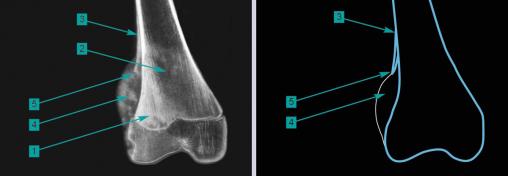

Infiltration tumorale condensante (1), hétérogène, associée à quelques plages lytiques irrégulières (2) et à une réaction périostée (3) en partie lysée par l'expansion "en feu d'herbe" dans les parties molles (4) dessinant l'éperon de Codman (5).Ces aspects sont ceux d'un processus agressif, malin, très préoccupant et imposant un avis spécialisé en urgence.